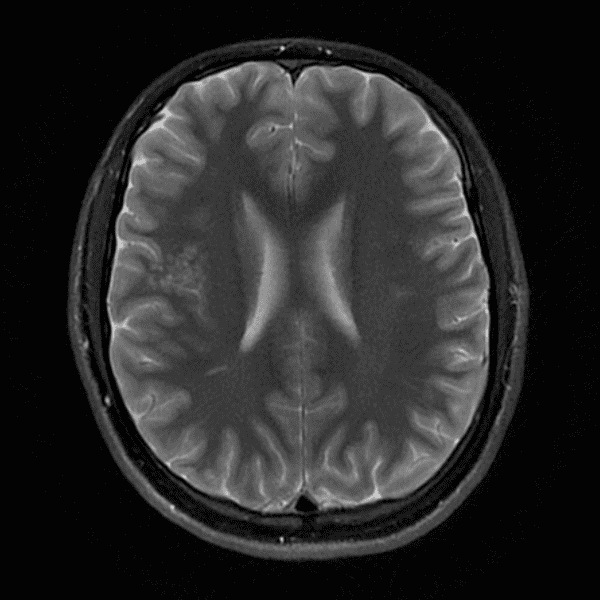

Classic Cases